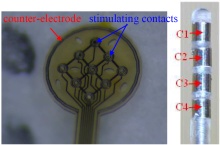

Electrical Stimulation is widely used today for Deep Brain Stimulation treatments and retinal prostheses. The Electrical Double Layer formed at the interface between the electrode surface and the extracellular medium is considered thru the linear Helmholtz model and the nonlinear more ... 詳細を見る